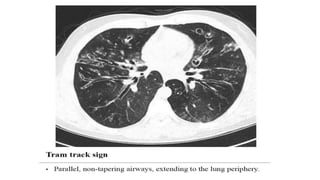

 Usually based on presentation +

radiographic findings

 Chest radiography lacks sensitivity

 CT – more specific